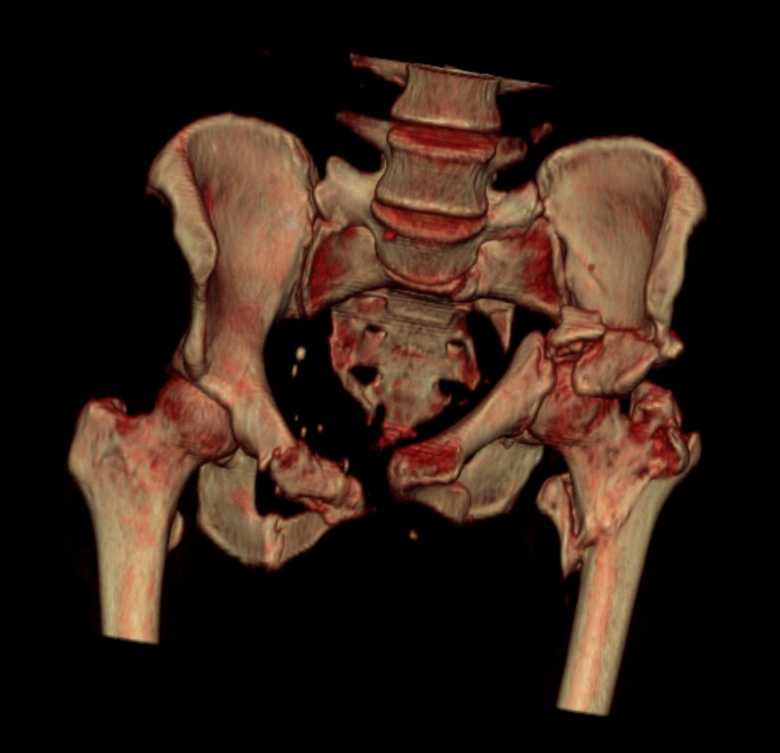

Больная 43 года (промышленный альпинист), 28.07.08 в результате падения с 5 этажа получила политравму: Перелом свода и основания черепа. Вертикально-нестабильное повреждение таза, осложнённое разрывом мочевого пузыря. Чрезвертельный перелом левого бедра. Перелом правой таранной кости, переломовывих правой кубовидной кости. Тупая травма живота, разрыв печени, ушиб почек. Забрюшинная гематома. В день травмы - лапаротомия, ушивание ран печени. Разрыв мочевого пузыря не диагностирован. Течение болезни осложнилось развитием мочевого затёка и обширной пред- и забрюшинной флегмоны, сформировался свищ мочевого пузыря. 19.8.2008 вскрытие, дренировние флегмоны, ревизия мочевого пузыря, обтурация мочевого свища (свищ закрылся в октябре), 1.10.2008 некрэктомия, пластика по Шеде-Лидскому правой кубовидной кости. По результатам КТ диагностирован рак правой почки (диагностическая находка), 8.10.2008 нефрэктомия справа. Переломы велись консервативно. Имеется вертикальное смещение левой половины таза с выраженным отведением крыла (клинически подвижности нет), несросшийся низкий двухколонный перелом левой вертлужной впадины с потерей конгруэнтности, укорочение около5 см, застарелый разрыв лонного сочленения, неправильно сросшиеся переломы обеих ветвей правой лонной кости с укорочением, патологическая подвижность лоно-седалищного фрагмента слева. Правая нижняя конечность неопорна, несмотря на то, что лежа прямую ногу поднимает, ходит на левой ноге (ортопедическая обувь) с костылями, справа тазобедренный ортез. Седалищные нервы работают.Урологи отпустили больную на 6 мес.